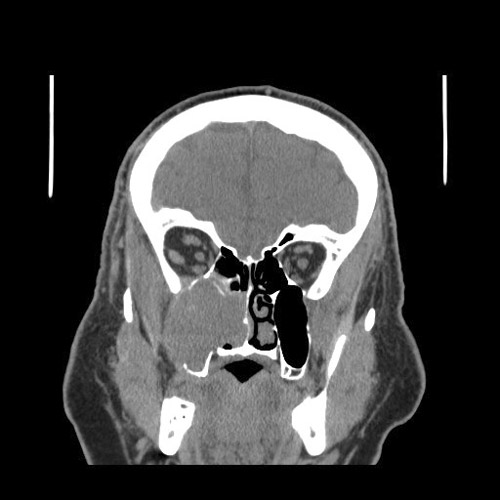

Clinical information: The patient was a 65 year-old man was referred to our institute because of a large mass in his right maxillary sinus with extension to the ethmoid sinus, and the orbit. A biopsy was performed. The patient was treated with radiaiton therapy and a hemi-maxillectomy with enucleation of the right globe was performed.

There

was

large destructive mass

(Panel

A)

that

occupied

the bulk of the space of the right maxillary sinus with destruction of the floor

of the orbit and anterior wall of the maxillary sinus. Invasive fungal infection

could

generate this type of picture but the clinical story

did

not go along with it. A malignant tumor

the most likely diagnosis in this case.

The epicenter of the tumor did not seem to be of osseous origin. This made

osseous based tumors such as osteosarcoma and hematopoietic tumors such as

lymphoma and plasmacytoma less likely. With this type of growth pattern and the

location both taken into consideration, an epithelial neoplasm, most likely a

carcinoma, was the leading differential diagnosis.

A. CT |